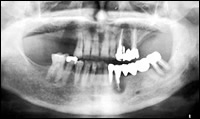

最近のインプラント治療は、以前のように、噛めることを優先とした治療だけでなく、見た目(審美性)まで考慮した治療へと移行してきています。また、以前までは、骨がない部分にはインプラント治療はあきらめざるを得なかったところに、骨を再生させ、骨量を増大させることによりインプラントを植立することが可能になってきています。しかし、このような治療には術者の高度な技術が要求されるのも確かです。

また、インプラント治療を受けられる患者さんでは、その他の歯牙や歯周組織においても問題を抱えている場合が多く、一口腔単位での治療が必要になる場合がほとんどであるといえます。噛み合わせや歯の根っこの治療(根間治療)、歯周治療、虫歯の治療をおろそかにしてインプラント治療の成功は望めないといっても過言ではないでしょう。 |